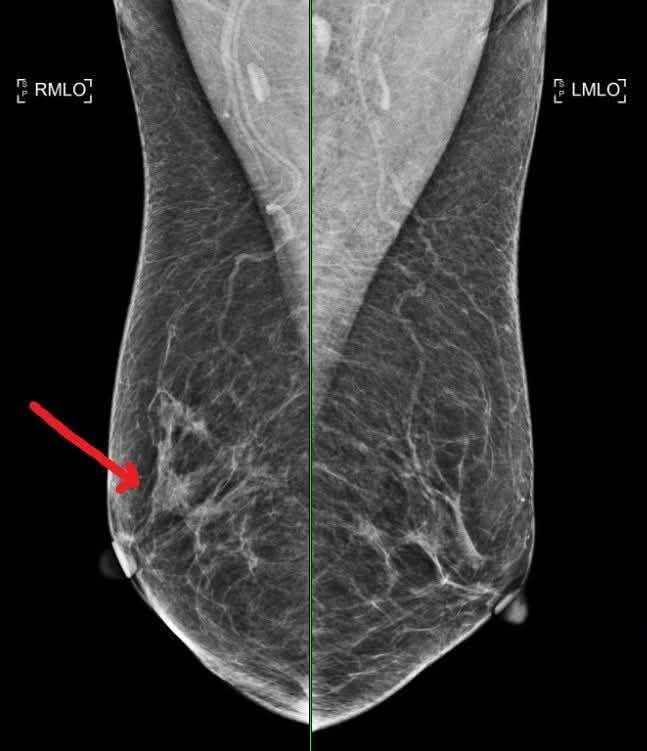

หน้าหลัก > ความรู้ทั่วไป ความรู้ทั่วไป 16 พ.ย. 2568 เลือดจาง” ไม่ใช่แค่ซีด — แต่มันคือภาวะที่ร่างกายขาดออกซิเจนเรื้อรัง 29 ต.ค. 2568 นี่คือสภาพใยประสาทในสมองคุณที่เต็มไปด้วย ‘ขยะพิษ’ (β-amyloid) 31 ส.ค. 2568 "การตรวจที่จำเป็นและเหมาะสม" เป็นสิ่งที่เพียงพอแล้ว 21 ส.ค. 2568 3 สิ่งง่ายๆ ที่ช่วยลดความเสี่ยงมะเร็ง 19 มิ.ย. 2568 📌 สรุปวิธีสร้างฮอร์โมนไทรอยด์ กว่าจะได้ ไม่ได้ง่ายๆ นะเออ 17 มิ.ย. 2568 เมื่อประมาณ 42,000 ปีก่อน มีสิ่งผิดปกติเกิดขึ้นกับ สนามแม่เหล็กโลก 5 มิ.ย. 2568 ⚠️ ขาบวมแดงข้างเดียวแบบนี้ เกิดได้จากหลายโรค อย่าปล่อยไว้ โดยเฉพาะโรคแรก เสียชีวิตได้ 14 พ.ค. 2568 อ้วน คือ 1 ในสาเหตุที่ทำให้นอนกรน 28 เม.ย. 2568 4 วูบ สถานการณ์ต่างๆ เกิดจากกลไกใดบ้าง มาดูกัน 25 เม.ย. 2568 “หมอประชา” ไขข้อสงสัย ร้อนจัดดื่มน้ำเย็นๆ ทำเส้นเลือดสมองแตกจริงไหม? 20 เม.ย. 2568 อย่า …ขู่ให้ลูกหยุดร้องไห้ …. 30 มี.ค. 2568 1